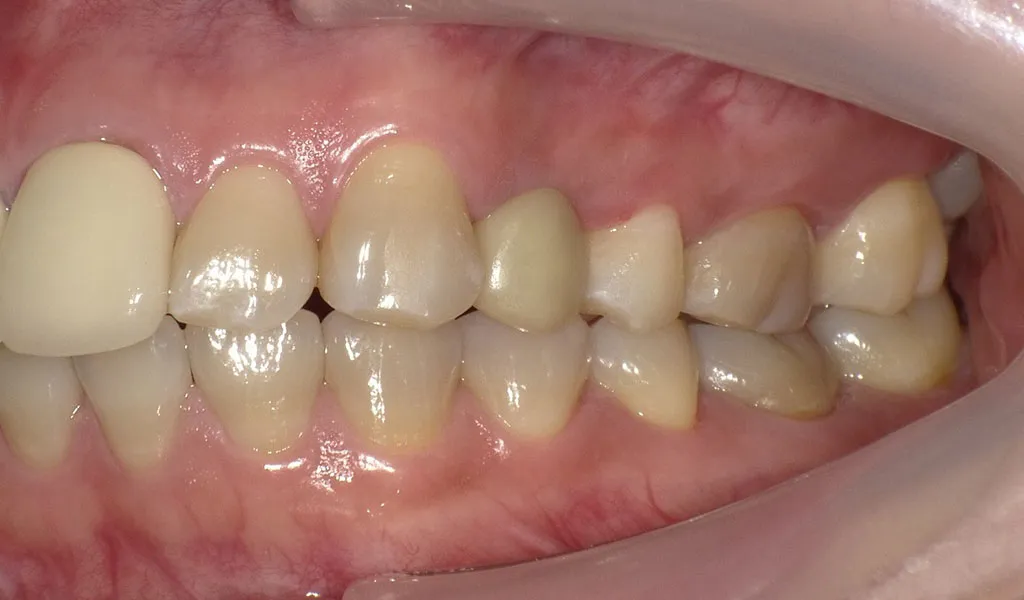

Before

After

奥歯1本のインプラント治療

30代女性

治療期間:4ヶ月

費用:総額37.4万円(検査・診断・手術関連処置費用等を含む)

リスク:出血、腫脹、疼痛、神経麻痺、補綴物の脱落、破折、インプラント体の破折、咬合違和感、インプラント周囲炎など -